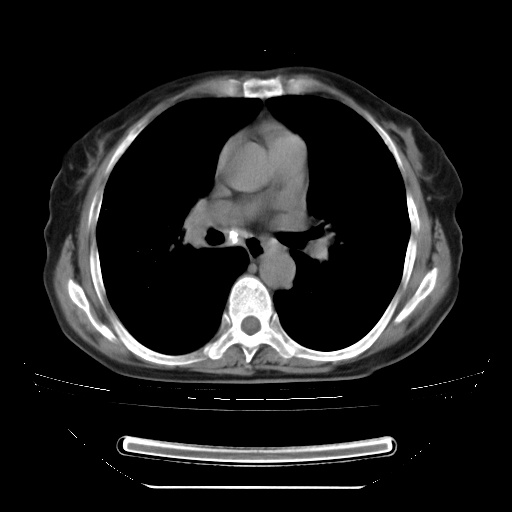

查原发灶吧,肺内转移瘤!肝内也有病灶,需强化明确。

以下是引用zsl6918在2009-3-5 23:00:00的发言:[br]查原发灶吧,肺内转移瘤!肝内也有病灶,需强化明确。

两肺内病灶呈小结节状和树芽状,纵膈的肿大的淋巴结密度不均匀,并见有钙化,考虑为两肺结核可能更大些。

两肺内病灶呈小结节状和树芽状,纵膈的肿大的淋巴结密度不均匀,并见有钙化,多形态病灶,考虑为两肺结核,肝内考虑小囊肿。

增殖性多发性病灶,大小不一,分布不均匀,发生于肺泡中,纵隔淋巴结肿大其内有钙化,诊断:细支气管肺泡癌,

病灶以结节为主,大部分边界清楚,分布不均,病灶形态较单一,偶见空泡征,纵膈淋巴结肿大钙化,无结核中毒症状考虑 感染性病变【真菌类可能性大】,细支气管肺泡癌。其他待排

片子很好,质量很高,两侧肺门淋巴结肿大并有钙化,两肺弥漫病灶,首先考虑tb并播散,但年龄大了呀(72岁)小细胞肺癌不能除外,如果是肺癌也没什么大的治疗了,建议正规抗结核治疗后复查

纵隔见肿大淋巴结并钙化,首先考虑结核,但感觉小结节像“挂果”征,分布位于支气管边缘,所以不排外肺泡癌,建议抗唠后复查吧?不然是癌的话,也不好治吧?化疗?

以下是引用zhw974247在2009-3-6 6:25:00的发言:[br]两肺内病灶呈小结节状和树芽状,纵膈的肿大的淋巴结密度不均匀,并见有钙化,多形态病灶,考虑为两肺结核,肝内考虑小囊肿。